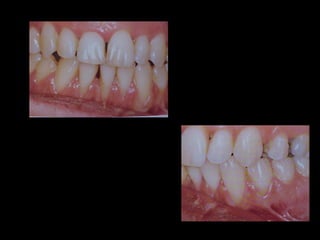

Antes (arriba) Después (derecha)

La paciente fuemanejada iatrogénicamente por 5 años Utilizando diferentes implementos ortodóncicos La regla es clara: Laterognatias de más de 2º son quirúrgicas